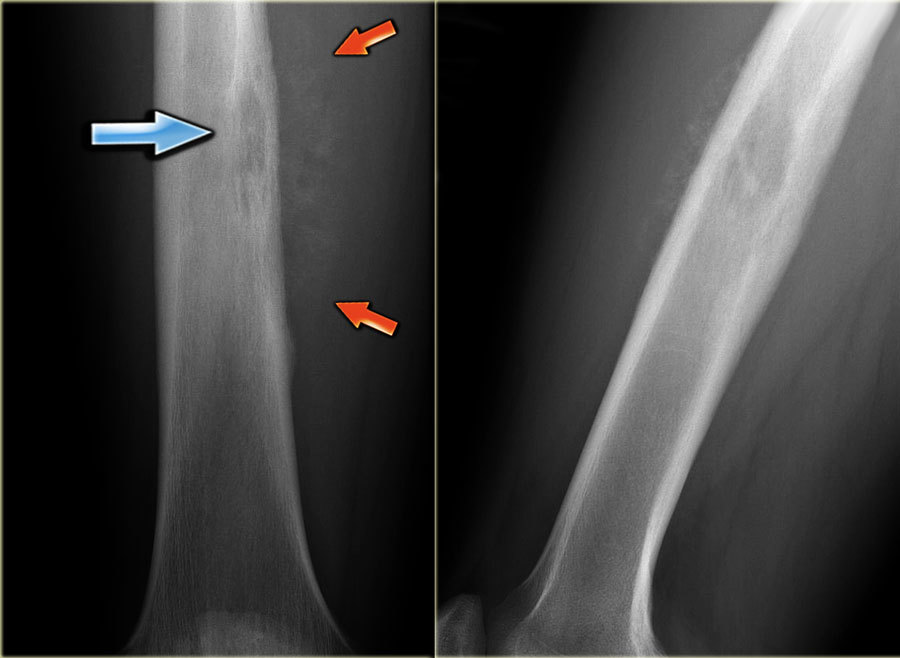

Describe the lesion. Differential? Diagnosis? Associated conditions?

Non-ossifying fibroma

Describe this XR. Differential? Diagnosis?

Differential for metaphyseal fibrous defect

Osteoid osteoma

Intracortical abcess

Stress fracture

Intracortical osteosarcoma